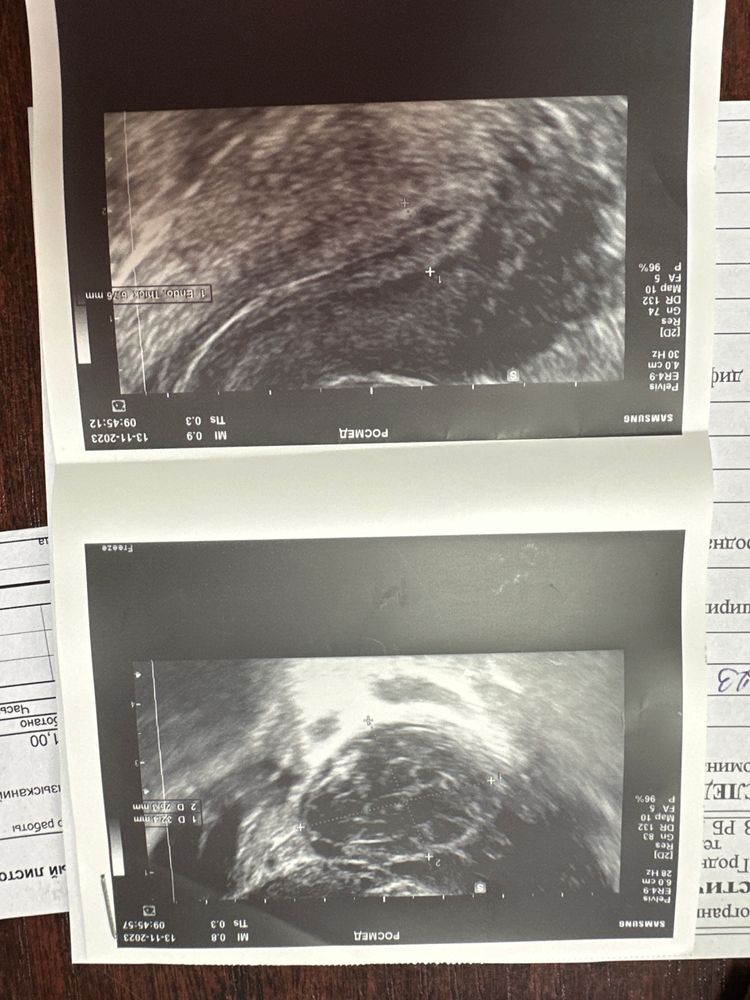

Алёна Хаустова, теперь вопросы по эндометрию (

Арина, если структура его хорошая, то и на 6мм беременнеют Я на 7,4мм забеременела, в беременность он становится толще

Изображение Алёна Хаустова,